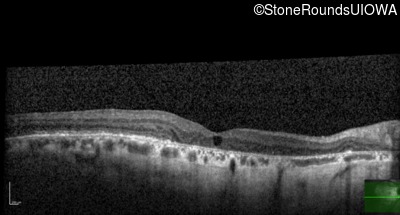

Foveal Hypoplasia (IIIG)

Highlighted Images

Diagnosis & molecular findings

Foveal Hypoplasia PAX6 Pro76Leu CCG>CTG   AD